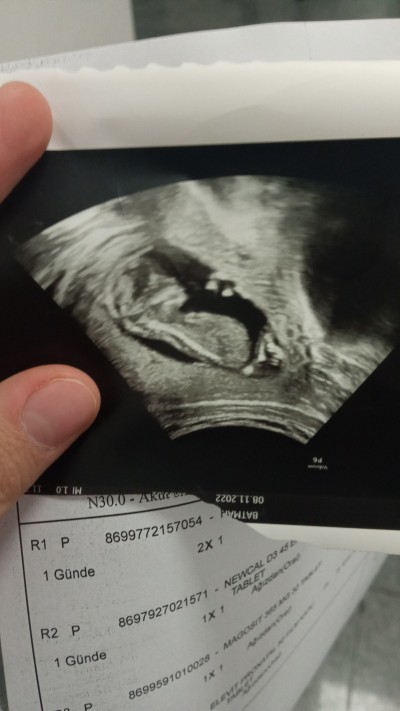

Kizlar bakar mısınız cinsiyet ten anlayan var mı ?

Gebelik haftası 16+4

Kıza benzettim sanki sağlıklı oldunda Allah gönlüne göre versin